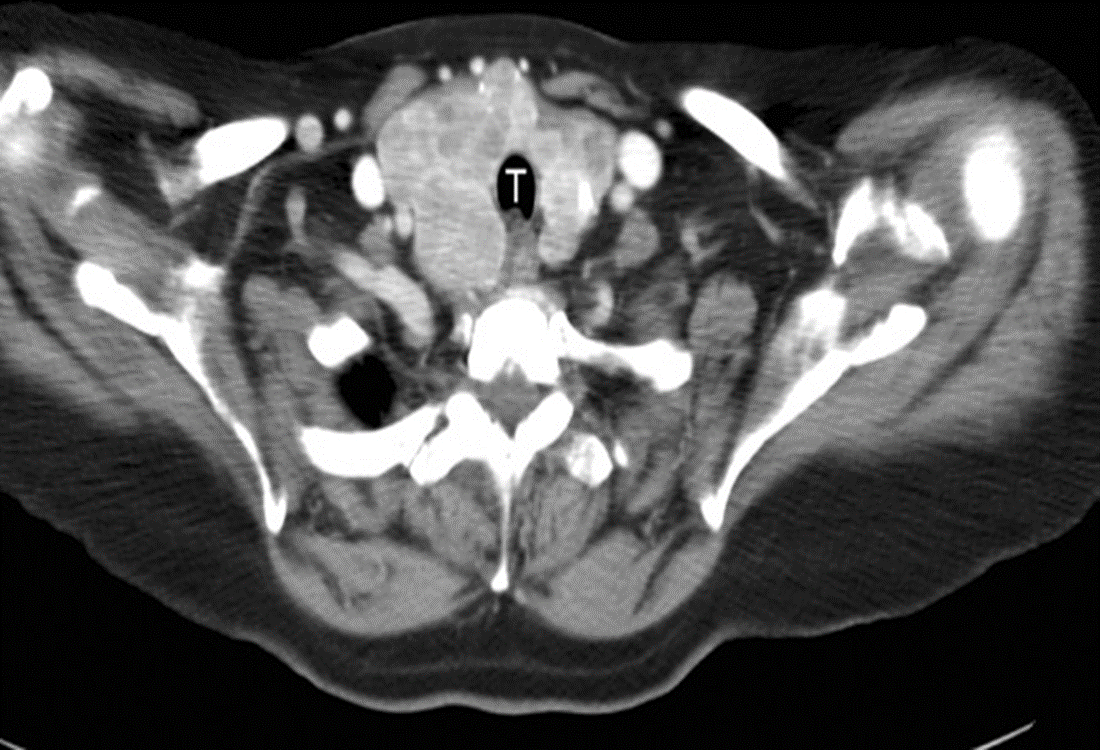

CT

The enlarged thyroid almost surrounds the trachea (T) and enhances avidly after intravenous contrast showing many nodules of varying size.